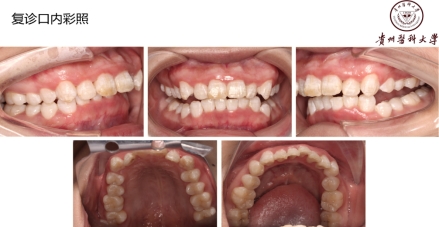

治疗以及预后:排除了白血病、艾滋等严重疾病,明确诊断后,病人也不要过分担心。这种病发病急,治疗效果及预后也好。治疗时去除牙石及坏死组织,局部止血,双氧水充分冲洗,口服抗厌氧菌药物替硝唑等,全身支持治疗:高蛋白饮食、维生素C等。一定要改变生活习惯,避免熬夜,戒烟,放松心情,保持口腔卫生!